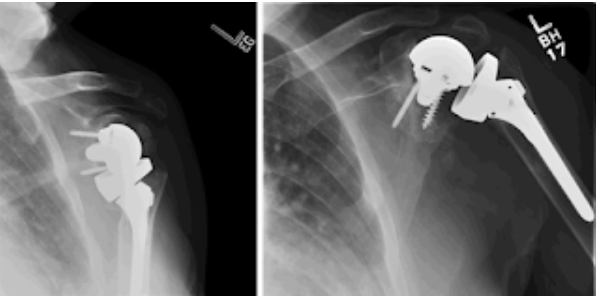

Four recently published articles provide important new information about the ream and run procedure for active patients with shoulder arthritis Those readers interested in learning more can access a discussion of these new articles here: shoulderarthritis.blogspot.com/2026/03/cocr-r…